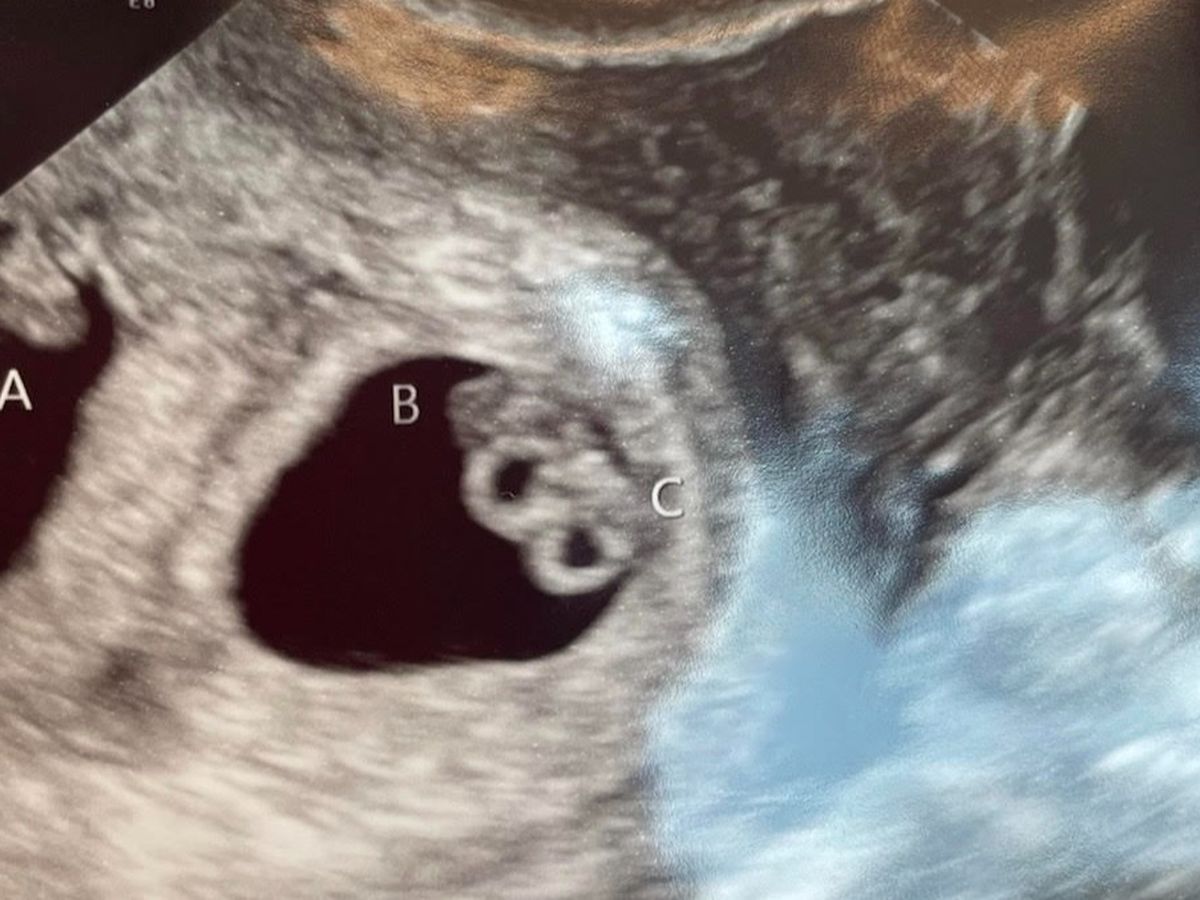

Hi everyone, thank you for taking the time to read our story of the babies and considering donating. We were so excited to get pregnant after getting married, however, we were not prepared for all the complications to come. At 6 weeks, we found out we were blessed with triplets. We have an identical set of girls and one boy. At around 7/8 weeks, I (mom) developed what is called hypermedia gravidarum, which is known as extreme sickness during pregnancy. This is not normal nausea, it is constant and wears the body down to where organs can even be affected. I was hospitalized 3 times for this, it was not until about week 16 that I got a Zofran pump that helped with my sickness. Each time it took a week or more before I would be out of the hospital. Due to the amount of time, I was going to the doctor, the ER, and getting infusions my husband and I had to quit our in-home daycare because it was not fair to those parents not to be able to provide proper and stable care for their children. Our car’s engine then went out as well. We then found out later on that Baby B, one of the girl twins is growth restricted and had elevated blood flow in her cord. This upped our doctors appointments to at least once a week, we also had to take a trip to Cincinnati Children’s Hospital to get extra testing done to make sure we didn’t need surgery to help the babies. We are now in the hospital for monitoring because Baby B is showing reversed blood flow and we need to be ready if they need to come out now. We are currently 27 weeks and trying to make it as close to 32 weeks as possible. With that being said, we are looking at being in the hospital for the 4th time now this pregnancy is for up to 5 weeks, then the babies will be in the NICU for at least 8 weeks. We were not prepared for the extensive amount of complications this would bring. We are seeking support due to having to quit our jobs and not being able to work at full capacity with all the complications we have been having. We still have a long journey ahead of us so anything will be appreciated! Thank you so much for your support and continued prayers.